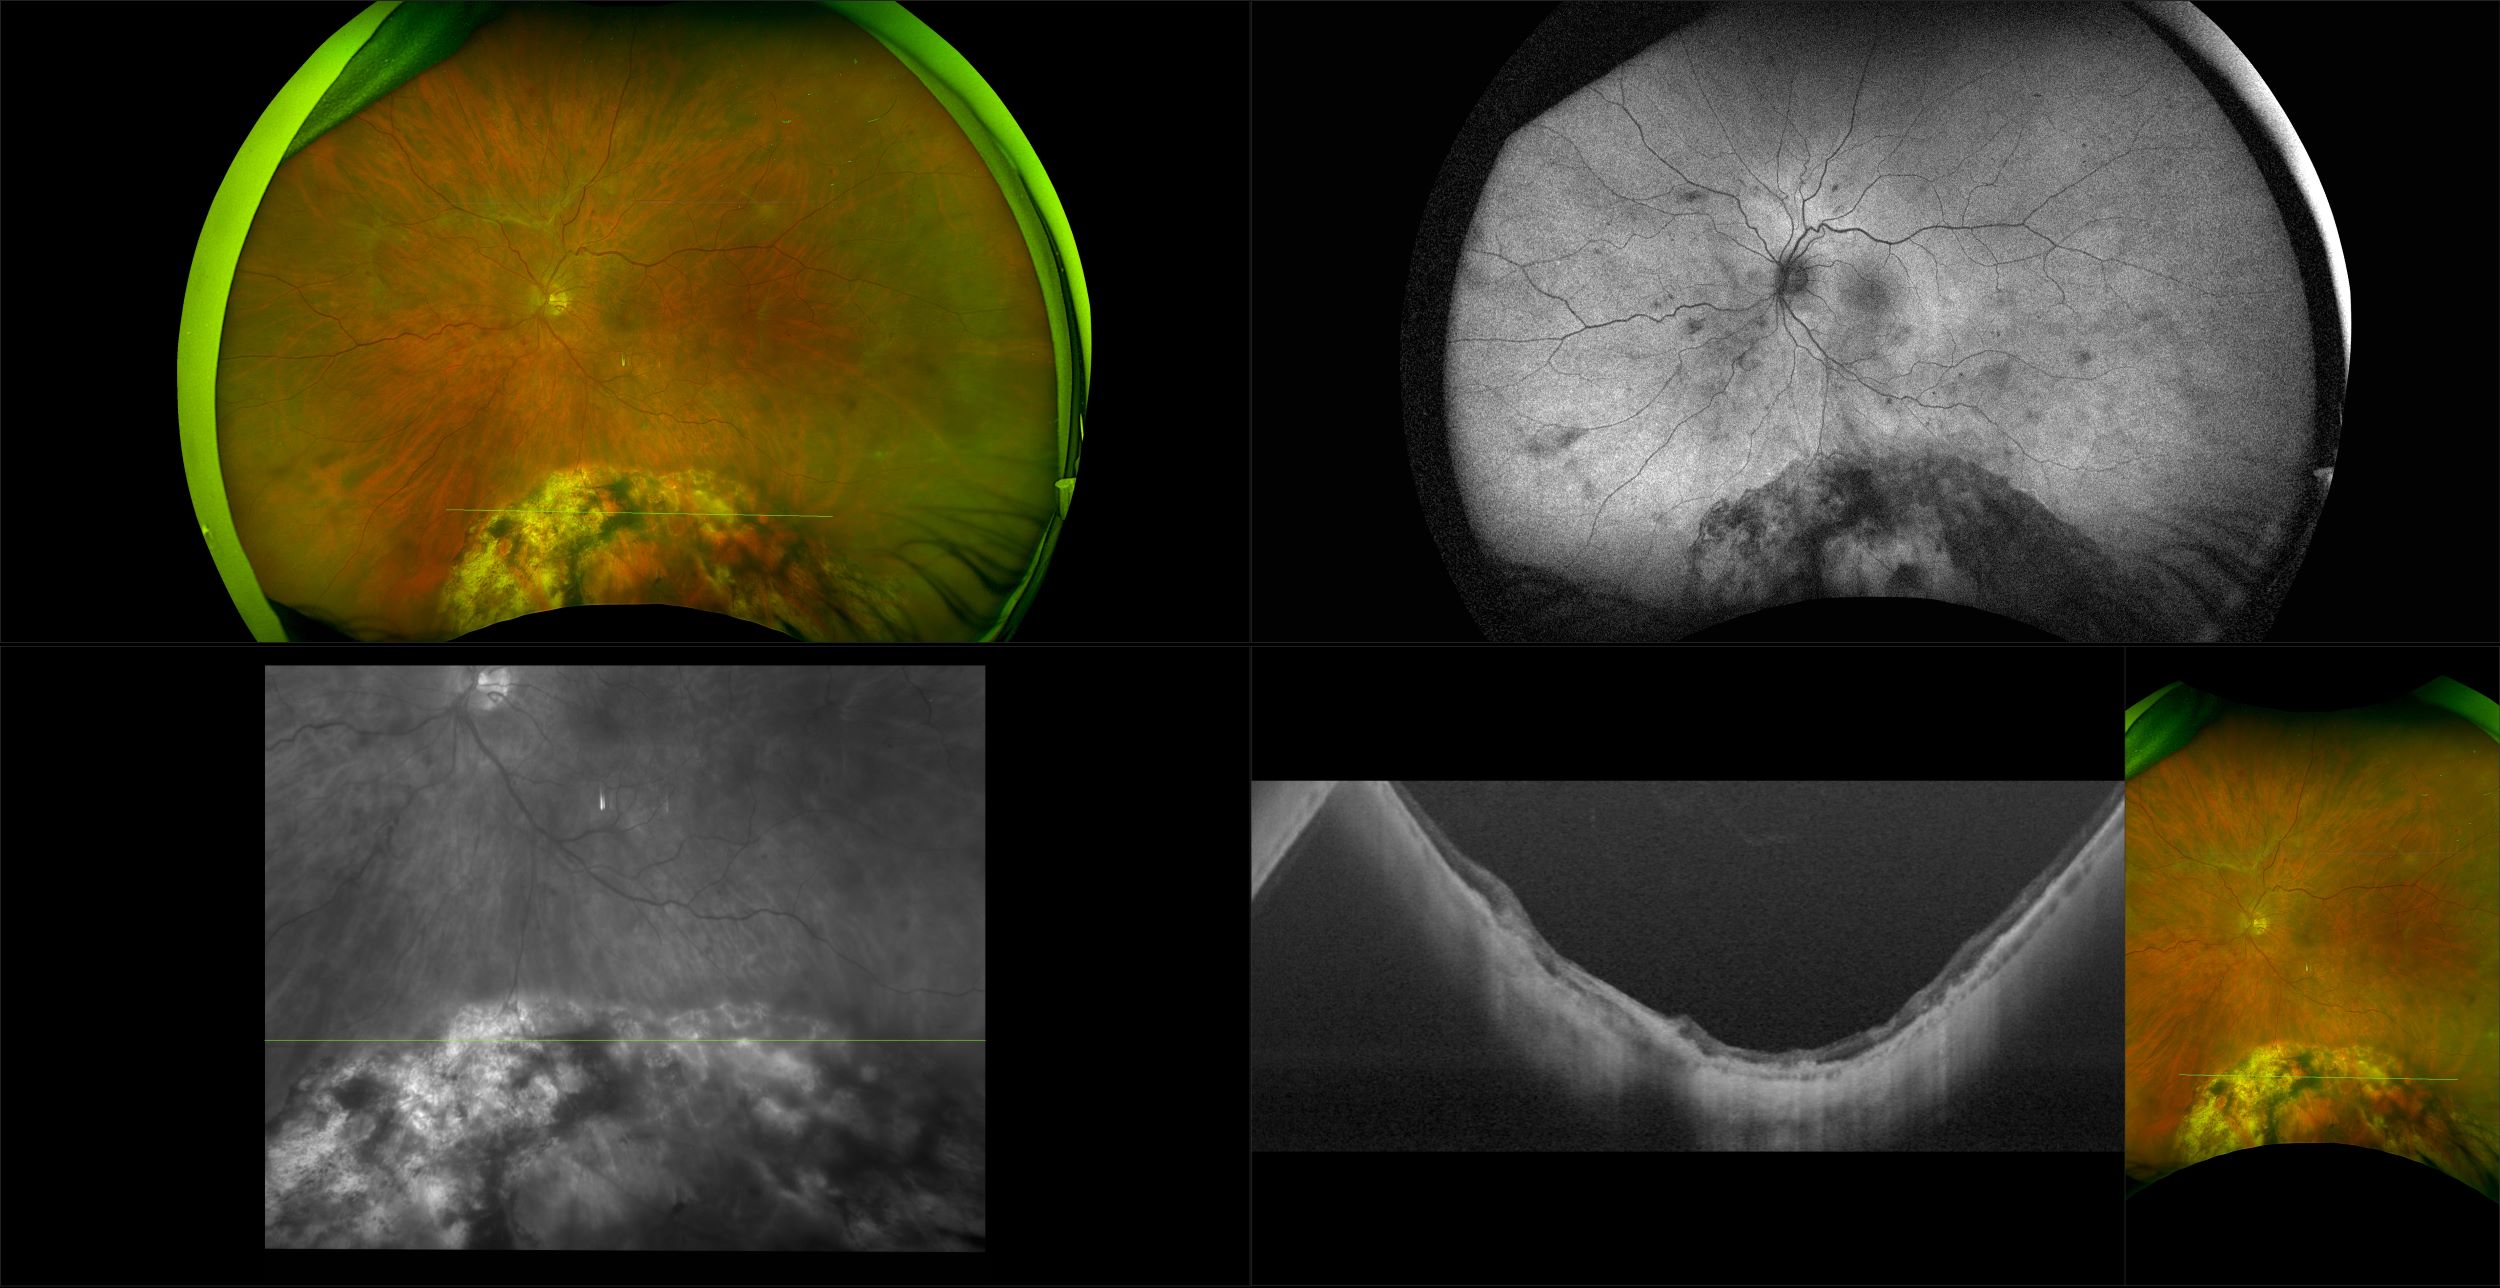

Monaco - Pigment Epithelial Detachment, RG, OCT

In some eyes, there may be small areas of the retina that are torn, or holes may develop. These areas, called retinal breaks, can lead to retinal detachment. Retinal breaks are often caused by traction from the vitreous, the gel that fills the back of the eye. Traction can occur as the vitreous pulls away from the retina, which occurs with age, trauma, surgery, inflammation, and near-sightedness.